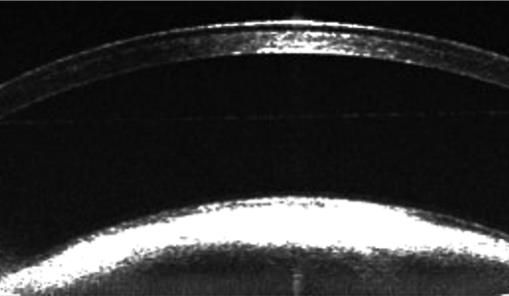

用于眼科动物模型的疾病筛查、病理学、药理学、药效学等方面研究。适用于各项眼科疾病、糖尿病、动脉硬化、高血压、干细胞等研究中视网膜结构的定量变化及定性分析。可对活体动物神经细胞,神经纤维层、微血管等微观结构改变进行早期、实时及长期无损伤的评估。

※ 1.6um高分辨率成像,实现更精准的病变及疗效评估;

4、用户自定义分层测量,实现脉络膜、感光细胞层更细分层次的厚度分析;

应用:眼节OCT成像及定量分析